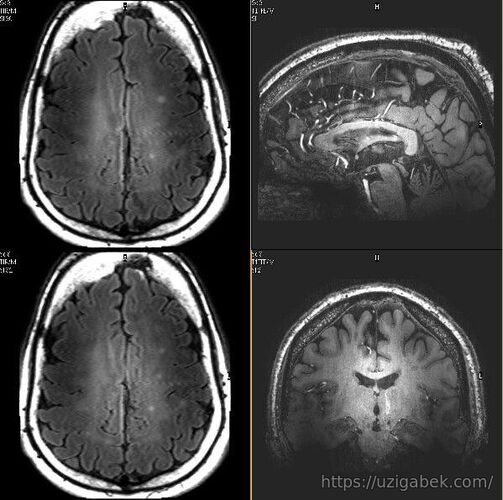

Miya Miya - insonning eng murakkab va eng kam o’rganilgan tana a’zosi. Biz u haqida ko’p tasavvurga ega emasmiz, ammo miya haqida ajoyib faktorlar yetarlicha.

1.Nerv impulsi 270 km/s tezlikka ega. 2.Miya ish faoliyati uchun shunday energiya kerakki, hatto uning quvvatidan 10 vattli lampochka yoqish mumkin. 3.Inson miyasidagi bir hujayra istalgan ensklopediyadan 5 marta ko’p ma’lumot saqlash kuchiga ega. 4.Qon aylanish sistemasiga kiradigan Kislorodning 20%i miya uchun sarflanar ekan. 5.Kunga nisbatan tunda inson miyasi faolroq bo’ladi. 6.Olimlarni aytishlaricha IQ darajasi baland odamlar ko’p tush ko’rarkan. 7. Neyronlar(miya hujayralari) insonni butun umri davomida o’sib rivojlanib boradi. 8.Axborotlar turli neyronlardan turlicha tezlikda tarqaladi. 9.Miyani o’zi og’riqni his qilmas ekan. 10.Miyaning 80%i suvdan iborat.